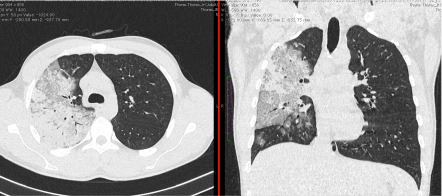

- Изменения при КТ (рентгенографии), типичные для вирусного поражения (объем поражения минимальный или средний; КТ 1 - 2)

- Изменения в легких при КТ (рентгенографии), типичные для вирусного поражения (объем поражения значительный или субтотальный; КТ 3 - 4)

- Изменения в легких при КТ (рентгенографии), типичные для вирусного поражения критической степени (объем поражения значительный или субтотальный; КТ 4) или картина ОРДС.

КТ имеет высокую чувствительность в выявлении изменений в легких, характерных для COVID-19. Применение КТ целесообразно для первичной оценки состояния ОГК у пациентов с тяжелыми прогрессирующими формами заболевания, а также для дифференциальной диагностики выявленных изменений и оценки динамики процесса. КТ позволяет выявить характерные изменения в легких у пациентов с COVID-19 еще до появления положительных лабораторных тестов на инфекцию с помощью МАНК. В то же время, КТ выявляет изменения легких у значительного числа пациентов с бессимптомной и легкой формами заболевания, которым не требуется госпитализация. Результаты КТ в этих случаях не влияют на тактику лечения и прогноз заболевания при наличии лабораторного подтверждения COVID-19. Поэтому массовое применение КТ для скрининга асимптомных и легких форм болезни не рекомендуется.

4. Все выявляемые при лучевых исследованиях признаки, включая КТ-симптомы, не являются специфичными для какого-либо вида инфекции и не позволяют установить этиологический диагноз. Вне клинической (эпидемической) ситуации они не позволяют отнести выявленные изменения к пневмонии COVID-19 и дифференцировать их с другими пневмониями и невоспалительными заболеваниями. Данные лучевого исследования не заменяют результаты обследования на РНК SARS-CoV-2. Отсутствие изменений при КТ не исключают наличие COVID-19 и возможность развития пневмонии после проведения исследования.